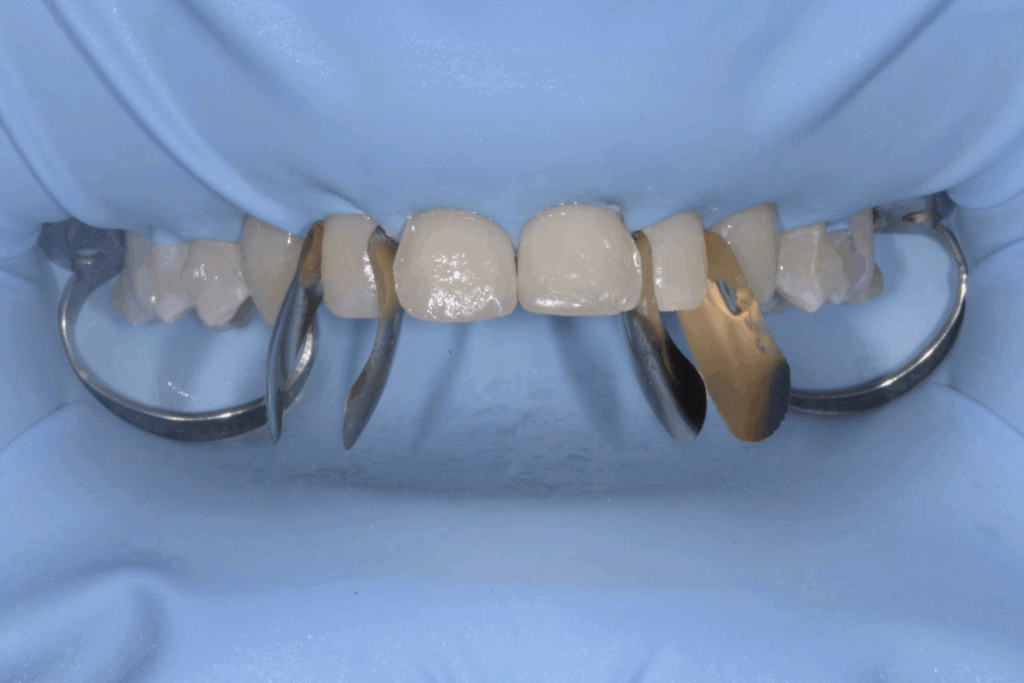

Fase 2: prima della ricostruzione in composito

Una volta completata la fase ortodontica, siamo passati alla finalizzazione estetica degli incisivi superiori. Utilizzando la tecnica della ricostruzione in composito, abbiamo aumentato le dimensioni dei denti, migliorandone la forma e l’armonia con il resto del sorriso. Il composito, un materiale estetico e versatile, ci ha permesso di ottenere un risultato naturale e duraturo senza sacrificare la struttura dentale originale.